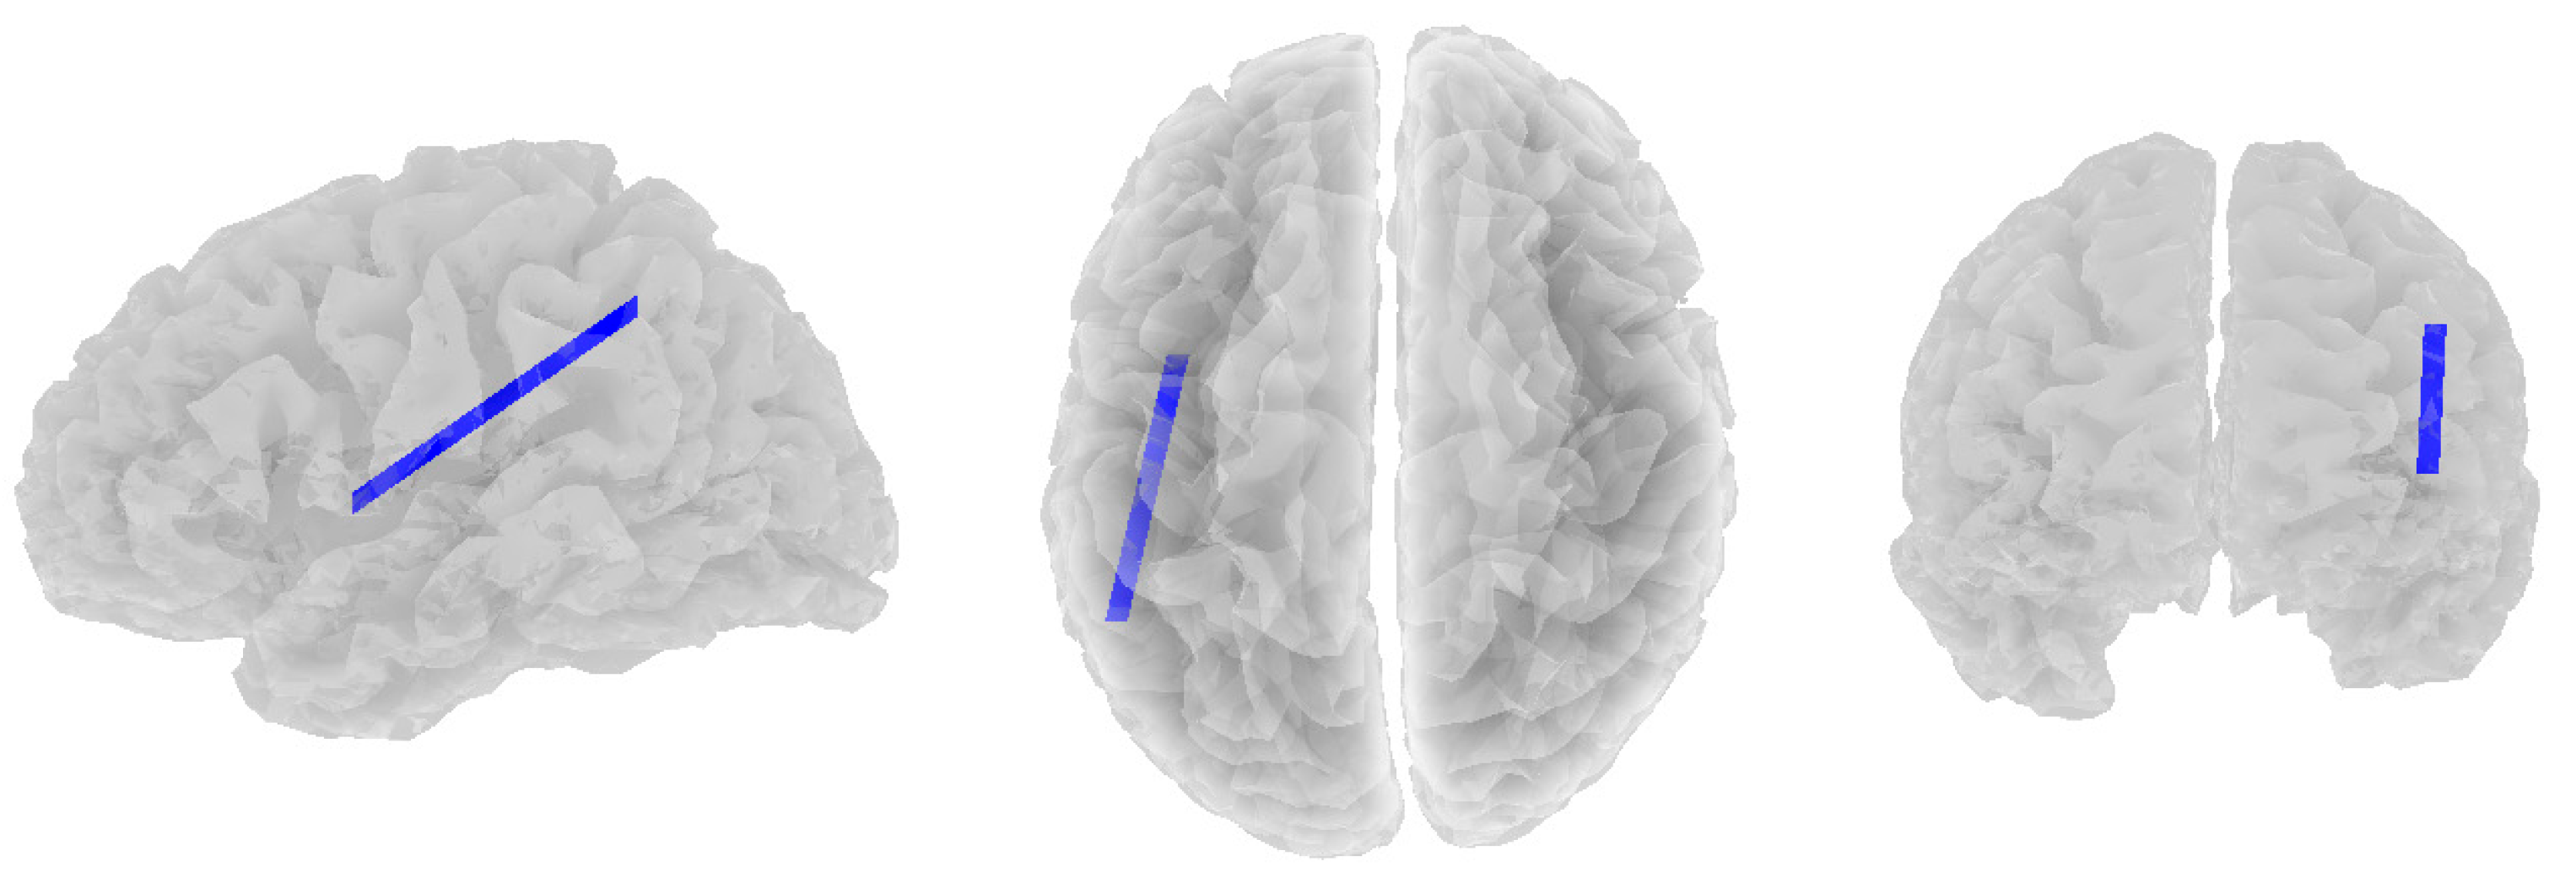

3.2. Alpha Band

3.3. Beta Band

3.4. Theta Band